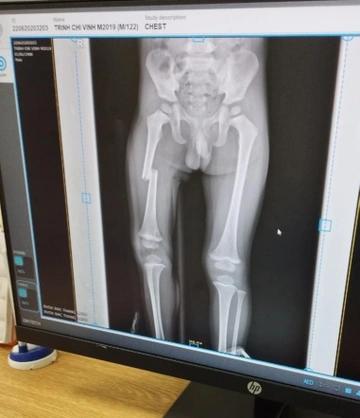

Anh N. cho biết, sự việc bắt nguồn từ việc cháu bé cầm chìa khóa của mẹ để chơi. Sau khi tìm không thấy, người phụ nữ bực tức, dùng chân đạp liên tục vào đùi con trai. Sự việc đực camera an ninh ghi lại.